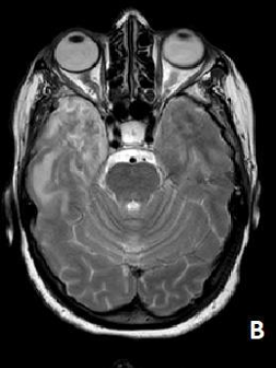

Atypical Location of Posterior Reversible Encephalopathy Syndrome (RPES): A Case Report

Anas Erragh, I Nabih, Y Hafiani, I Moussaid, S Elyoussoufi and S Salmi. 15(5): 36-38.